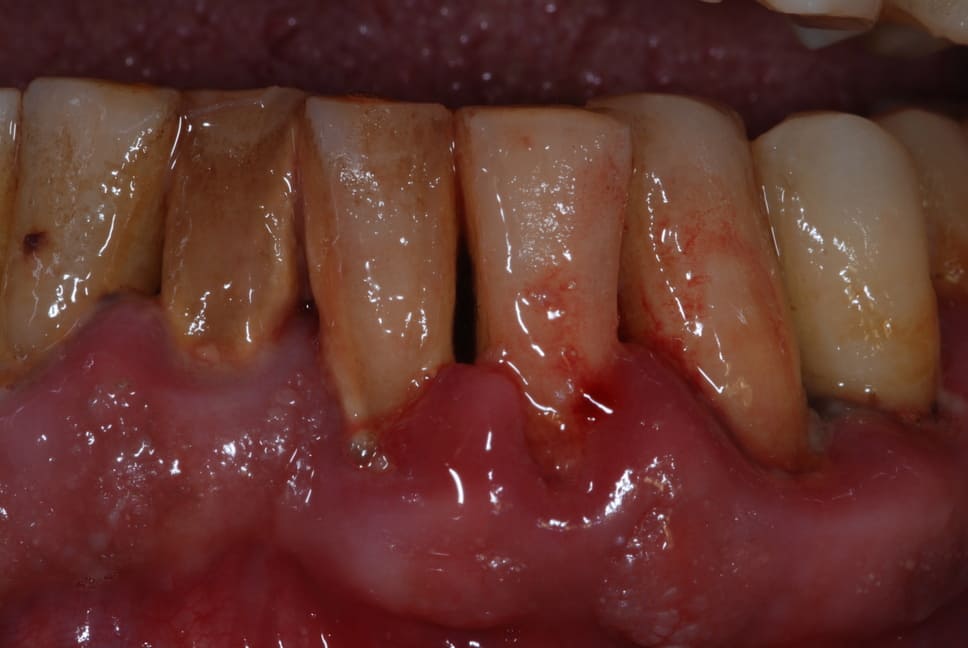

Misurazione tramite sonda della tasca parodontale

Gengive

Tasche gengivali e parodontite o piorrea

Read More